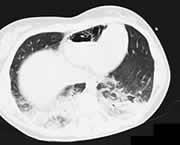

1名17岁女孩在交通事故中受伤,在被直升机转运到医院前,急救人员给她插入了一中心静脉导管。她因多发性损伤收入急诊室。胸部CT扫描显示,两肺挫伤,右心室内有空气。

空气栓塞是插入中心静脉导管罕见的并发症,但又是致命性的。在穿刺时或通过开放的静脉输液管,空气可进入中心静脉系统。空气大约以100 mk/秒的速度通过14G 针头。病人在交通事故后3日死于严重创伤。